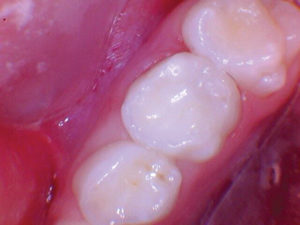

Caso 5

Una adolescente de 13 años presentada para un nuevo examen de paciente. Se observó una gran lesión cariosa en el primer molar permanente superior izquierdo, que presentaba síntomas de pulpitis reversible. Las opciones de tratamiento se discutieron con la paciente y su madre. Mis objetivos personales para este caso eran evitar la exposición de la pulpa y restaurar la forma y la función.

Figura 1. Presentación

clínica inicial del primer molar permanente superior izquierdo con caries

oclusal. |

Figura 2. Cuando la lesión

estaba sin techar, era evidente que había una lesión amplia y profunda. |